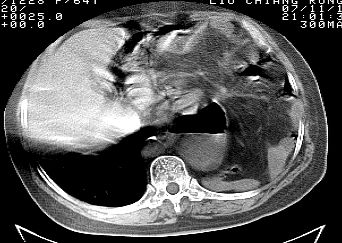

标题: CT10753:女, 64岁 隔疝 [打印本页]

标题: CT10753:女, 64岁 隔疝

女, 64岁 三十年前胸部外伤史, 间断胸闷,

典型左侧膈疝,疝出物为胃和大网膜,纵隔右移

稀钡剂造影就更好了

典型左侧膈疝,如此严重少见。